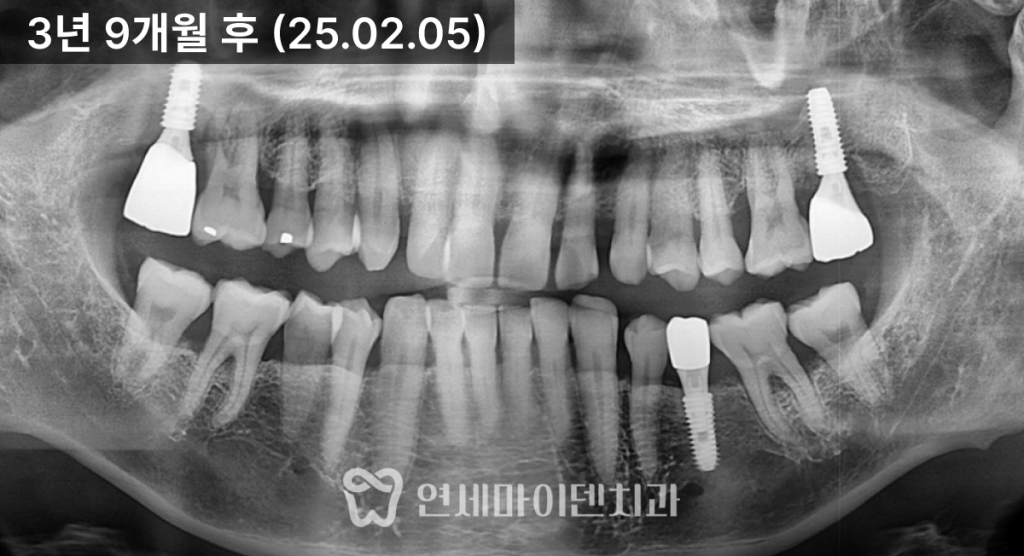

앞쪽 어금니의 흔들림도 눈에 띄게 줄어들었습니다.3년 경과 후 결과

치료 후 3년이 지난 현재까지도

임플란트, 보존한 자연치

모두 안정적으로 유지되고 있습니다.초기에는 뼈가 절반밖에 남지 않았던 부위가

뼈이식 후 건강한 높이로 회복되었고,

그 결과 임플란트 하나가

옆 자연치의 수명까지 함께 늘려준 셈이 되었습니다.